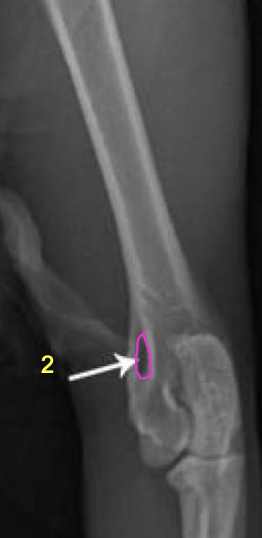

what is 1?

condyles of humerus

what is 2?

epicondyles of humerus

how does the olecranon process extend on a lateral view?

caudo-proximally

medial condyle is distal to the lateral condyle

where in the ulna is there a slight increase in opacity?

at the proximal extremity of the medullary cavity

where is the caudal ulnar cortex thicker?

in the proximal third of the diaphysis